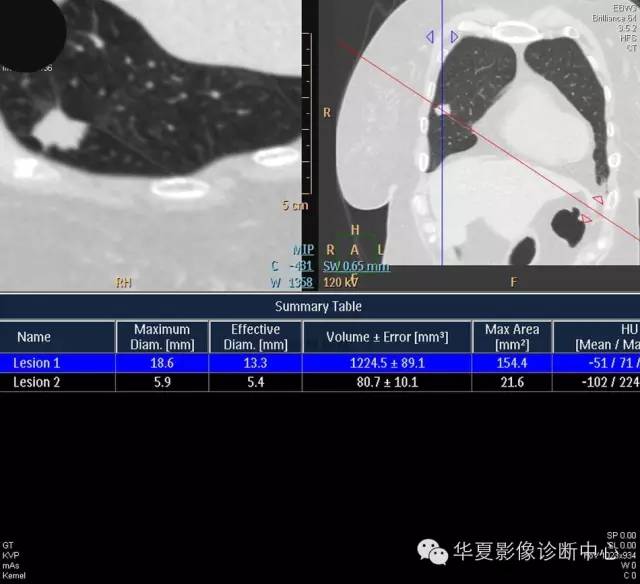

女,56岁,其父因肺癌去世,自觉胸部疼痛不适来诊要求拍胸片。

检查所见:

1.右肺上叶:肺组织1块,大小13×4×7cm。切面棕红色。2.右肺上叶肿物:灰白色组织一块,大小3×1×1.5cm。切面灰白色。3.右肺中叶结节:灰白色绿豆大组织1块。4.淋巴结:灰黑色绿豆大组织1块。

检查结论:

(右)肺中分化鳞状细胞癌。浸及胸膜。支气管残端切净。淋巴结未见癌转移(0/10)。